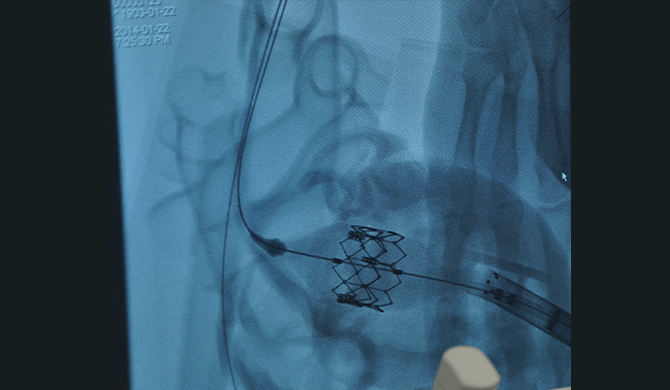

心疾患患者様の術前診断を

サポートする立体臓器模型

心疾患患者様一人ひとりのCTデータをもとに製作したCARDIO Simulatorは、

心臓の解剖学的構造を把握することができる医療機器です。

実物大の立体臓器模型のため、異常部位の場所や大きさ、周辺組織との位置関係などが明らかになり、

術前の診断を補完することが可能です。